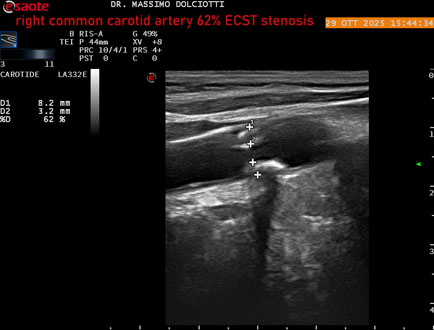

Data inserimento: 30/10/2025

Ecografia del: 29/10/2025

Strumento: Esaote MyLab Eight

Sonda: Lineare Multifrequenza 3-11 MHz

Età Paziente: F 75 anni

Motivazione dell'esame: controllo in pz con ateromasia carotidea ed ipercolesterolemia.

Commento all'esame: le immagini ed il video documentano all'arteria carotide comune destra placca disomogenea tipo 3 della classificazione di Gray Weale, che determina stenosi del 62% calcolato con metodo ECST.

Conclusioni: stenosi del 62% ECST dell'arteria carotide comune destra (62% ECST stenosis of the right common carotid artery).

Presentazione: Dr. Massimo Dolciotti - Ancona

Elaborazione digitale: Andrea Dini - Ancona